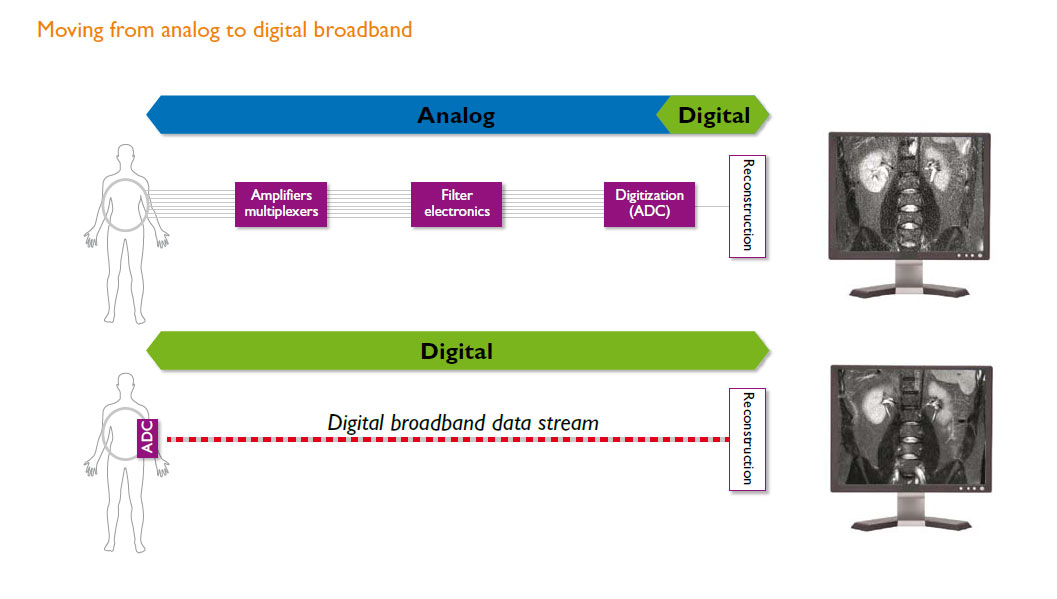

La tecnología dStream, arquitectura de banda ancha digital, digitaliza la señal directamente en la bobina.

Es posible obtener imágenes de gran calidad junto con una velocidad increíble gracias a nuestra arquitectura digital de banda ancha dStream. Disfrute de hasta un 40 % más de relación señal-ruido (SNR)* y un rendimiento mejorado con tecnología de radiofrecuencia independiente del canal que facilita las actualizaciones. dStream digitaliza la señal directamente en la bobina y elimina las influencias de ruido típicas de las vías analógicas, para capturar la señal del resonador magnético sin distorsión previa o compresión. Una conexión de fibra óptica de la bobina al reconstructor de imagen permite la transmisión de datos de banda ancha sin pérdidas.

La arquitectura de dStream utiliza un método de muestreo DirectDigital RF para la digitalización: la señal de imagenología de resonancia magnética (IRM) se muestrea directamente, sin conversión a CD. Esta técnica evita todas las etapas analógicas intermedias para la conversión descendente de la señal entre el elemento de la bobina y el convertidor de la configuración analógica a digital (ADC).

El resultado general es una arquitectura de recepción simplificada, con pocos componentes, bajo consumo de energía, alto y dinámico rango de SNR, y mejor estabilidad de señal y fase.

La digitalización tiene lugar en la propia bobina. La electrónica de la ADC ha sido miniaturizada y colocada dentro de la bobina.

Un cable de fibra óptica para cualquier número de canales de radiofrecuencia (RF) reemplaza múltiples cables coaxiales y mantiene la calidad de la imagen. El número de canales de RF ya no es una especificación del sistema.